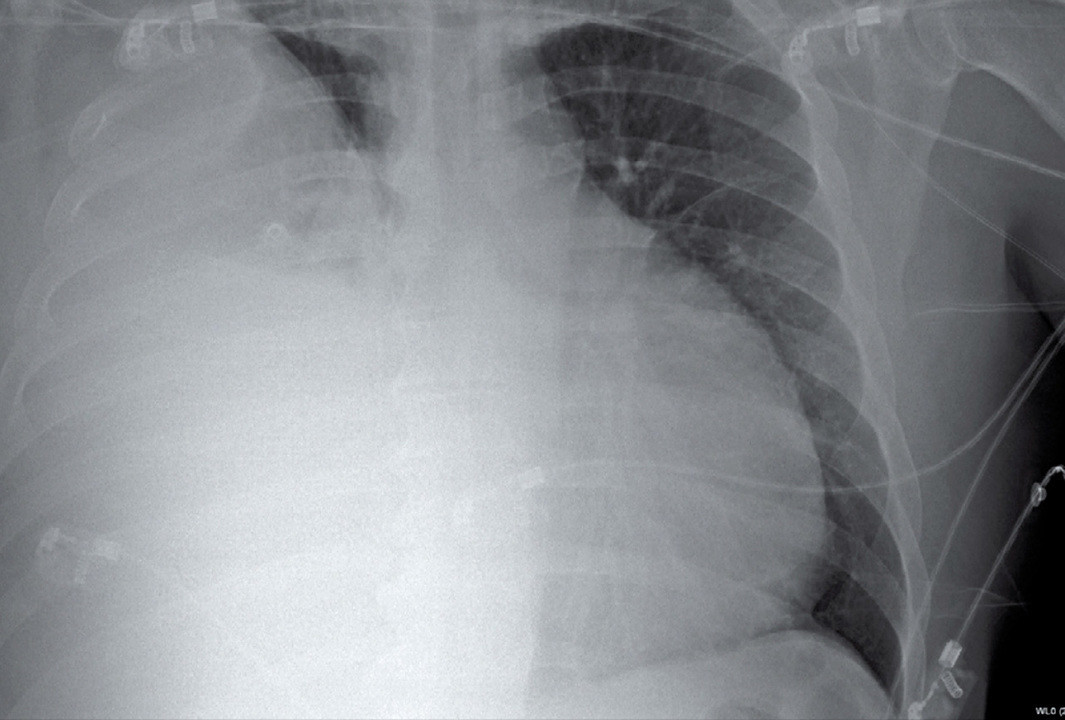

Фотографии бактерий, вызывающих бактериальные пневмонии у животных

Раздел: Другие животные